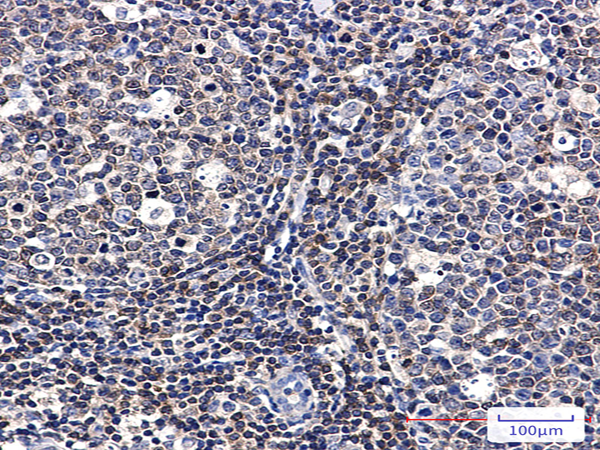

| IHC positive control: | Human tonsil |

| IHC Recommend dilution: | 50-100 |